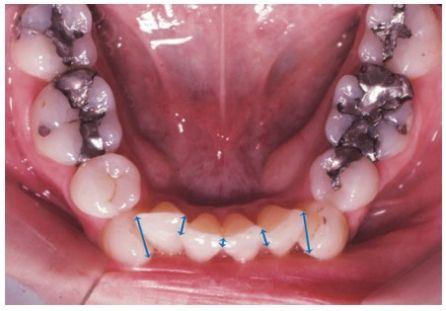

9.如圖所示,每一顆下顎門牙的接觸點(contact point)與相鄰牙齒應當接觸點距離的總和,稱為下列何者? (A)必要空間(space required) (B)可用空間(space available) (C)不整齊指數(irregularity index) (D)波頓指數(Bolton index)